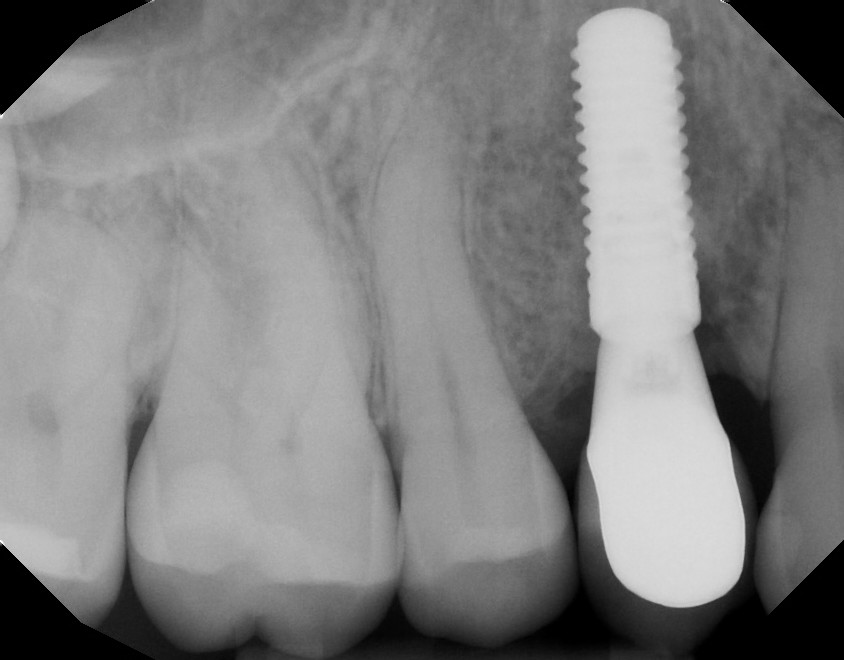

This mouth had recession on just one tooth with very little bone to support the tooth. The area needed support and thickness. The tissue was placed and the area now has thicker tissue to withstand the forces that the patient needs to place on it.